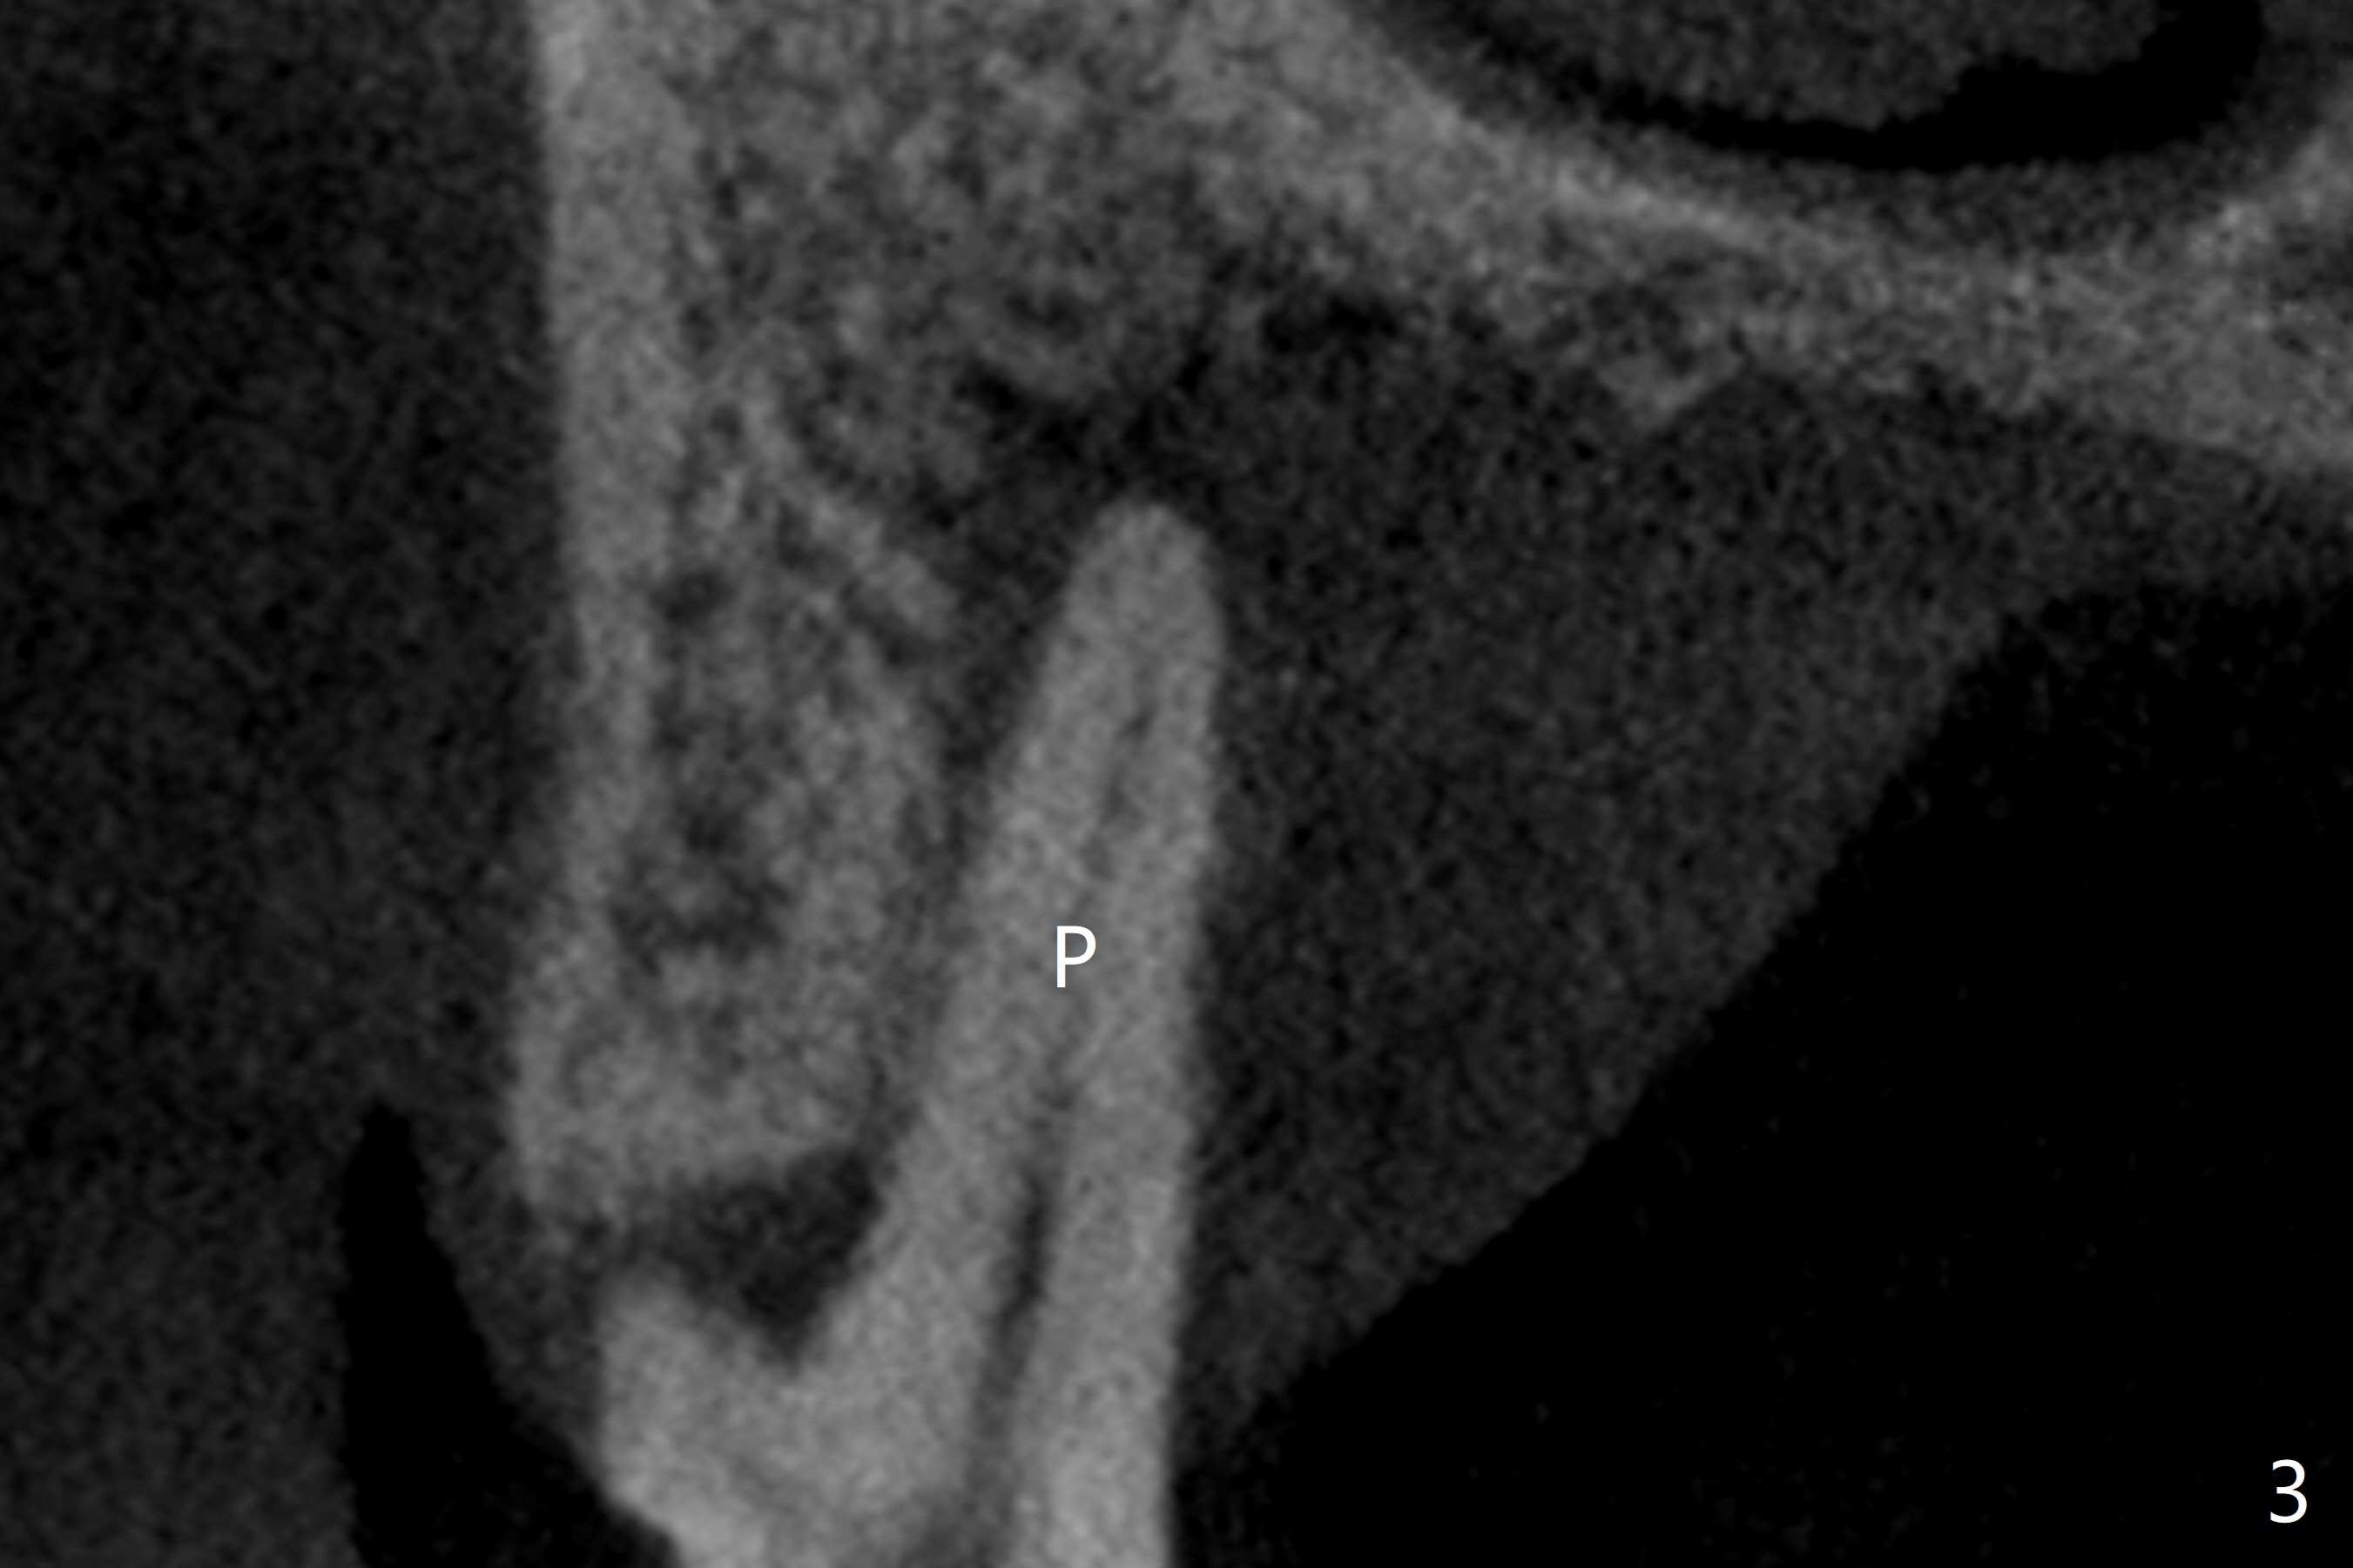

A 52-year-old man (smoker 1 ppd) has toothache in UR. The tooth #4 has severe Class V defect (Fig.1 *), periapical radio-lucency (PARL, arrow-heads) around the buccal roots and mild percu-ssion. PARL is more severe around the palatal root (Fig.2 P). Since it seems difficult to do socket preser-vation, can we do RCT to regrow bone before implant? CT coronal section shows the palatal defect of the palatal root (Fig.3,4), while sagittal one shows J defect of the palatal root, associated with root fracture (Fig.5). In fact the palatal root has transverse fracture at crestal level (Fig.6-8). The tooth #4 will be extracted for immediate implant (Fig.9,10); a 4 mm implant will be placed in the narrow space of #3 at the same time (Fig.11). The patient had symptoms consistent with aortic aneurysm. Since then smoke has been quit.